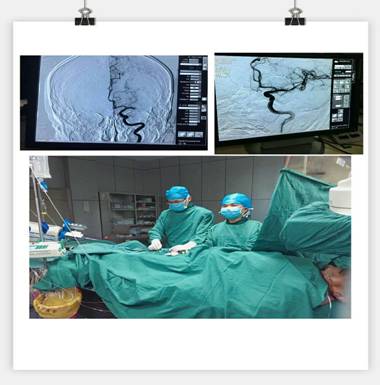

凌晨3點(diǎn)30分, “叮叮?!币魂嚰贝俚碾娫掜戔彺蚱屏松钜沟膶庫o。 “你好,這里是急診科,請準(zhǔn)備一張男床,腦血管意外患者”?;颊呤且幻?3歲男性,突發(fā)右側(cè)肢體乏力5.5小時,由家屬用輪椅推送入院。入科后患者神志昏睡,心率48次/分,血壓186/100mmHg,NIHSS評分20分。病人情況十分危急,在劉禮泉主任指示下,患者為急性缺血性卒中,有溶栓指征。在劉主任與家屬談話期間,值班醫(yī)生同時開出醫(yī)囑,患者予以硝普鈉控制血壓+尿激酶靜脈溶栓。夜班護(hù)士立即給病人抽血、吸氧、心電監(jiān)護(hù)、建立靜脈通道、準(zhǔn)備藥物……我們忙而不亂,默契配合。溶栓過程中劉主任一直守護(hù)在病人身旁,隨時觀察病人的病情變化。溶栓后,患者右側(cè)肢體有自主活動,但乏力癥狀及意識障礙無明顯緩解,劉主任立即決定行頭頸聯(lián)合CTA,明確是否有大血管閉塞。果不其然,患者頭部CTA提示左側(cè)大腦中動脈M1段栓塞,如果大血管得不到及時開通,必然會出現(xiàn)災(zāi)難性的后果。劉主任建議家屬考慮是否行血管內(nèi)治療開通血管,經(jīng)過耐心細(xì)致的溝通,患者家屬同意行急診腦血管造影檢查及血管內(nèi)治療。 同時立即召集曾比賢副主任、聶利珞副主任趕來醫(yī)院,為患者在局麻下行全腦血管造影+顱內(nèi)血管取栓術(shù)。時間伴隨著沉悶緊張的氣氛一分一秒地過去,取栓的生命通道終于打開,患者病變血管恢復(fù)良好,手術(shù)圓滿成功,此時灰暗的天才微微光亮……

在急性腦梗死患者緊急救治中,時間就是生命,該病例運(yùn)用了動靜脈聯(lián)合的方式治療急性腦梗塞,有效地保護(hù)了患者的大腦,此類技術(shù)在國內(nèi)處于領(lǐng)先治療手段,溶栓、取栓同步進(jìn)行的橋接搶救措施起到了至關(guān)重要的作用。該病例成功取栓意味著我院神經(jīng)內(nèi)科在治療急性腦血管病方面已經(jīng)從傳統(tǒng)的靜脈溶栓向介入取栓的現(xiàn)代化治療方式轉(zhuǎn)變。